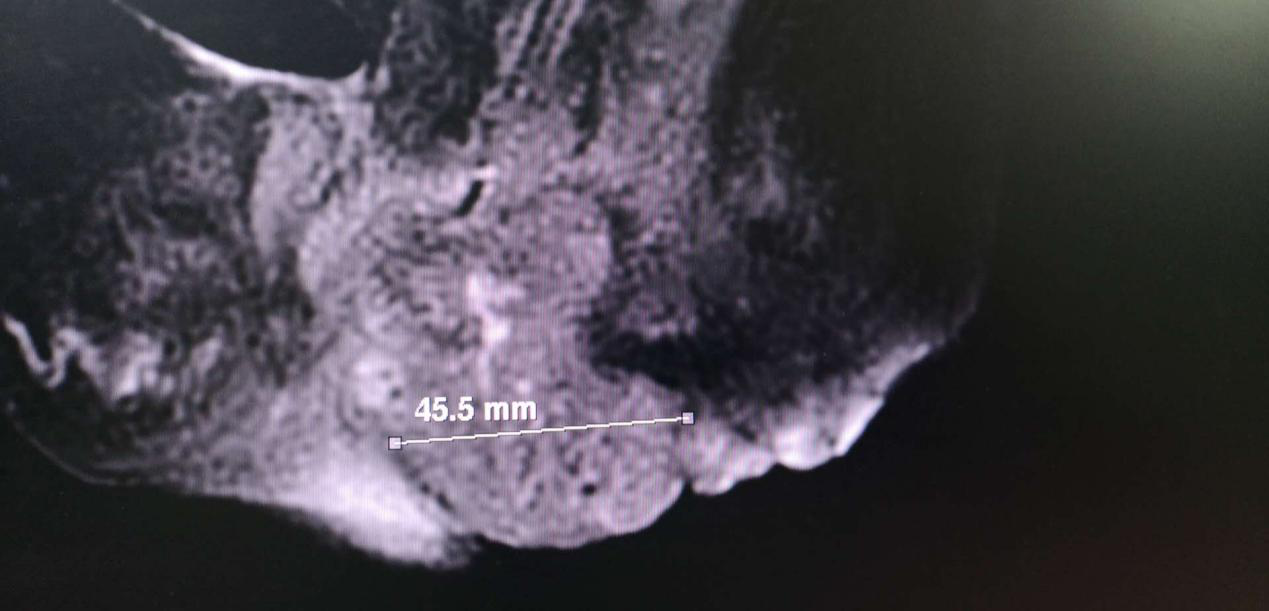

图一

6个月前,92岁的患者杜某因外阴阴道出现肿物伴局部破溃、疼痛等症状,曾赴北京多家三甲医院就诊,经诊断是外阴阴道癌,但因患者年龄高,基础疾病较多,难以支持手术、放疗、化疗等原因均被医院拒绝收院治疗。而患者病情日益加重,因疼痛苦不堪言,四处求医,于2020年4月14日来到我院就诊,经诊断患者外阴阴道恶性肿瘤、心功能不全、急性冠脉综合征、冠状动脉粥样硬化性心脏病、高血压3级、陈旧性脑梗死、脑动脉硬化、听力减退、胆囊息肉、右肾积水伴输尿管结石、下肢动脉血栓形成、胫动脉狭窄、电解质紊乱、呼吸性碱中毒。门诊以“外阴阴道恶性肿瘤“收入院。入院时:精神欠佳,时有心慌胸闷气短,时有头晕,走路时自觉腿部疼痛,夜尿频,便秘。近2月体重明显下降。既往:冠心病、高血压病史50余年,平素口服降压及扩血管药物,血压控制较好,但心脏功能欠佳,时有心慌胸闷,平素自行于家中吸氧后好转,22年前有脑血栓病史,近3-4年听力下降。